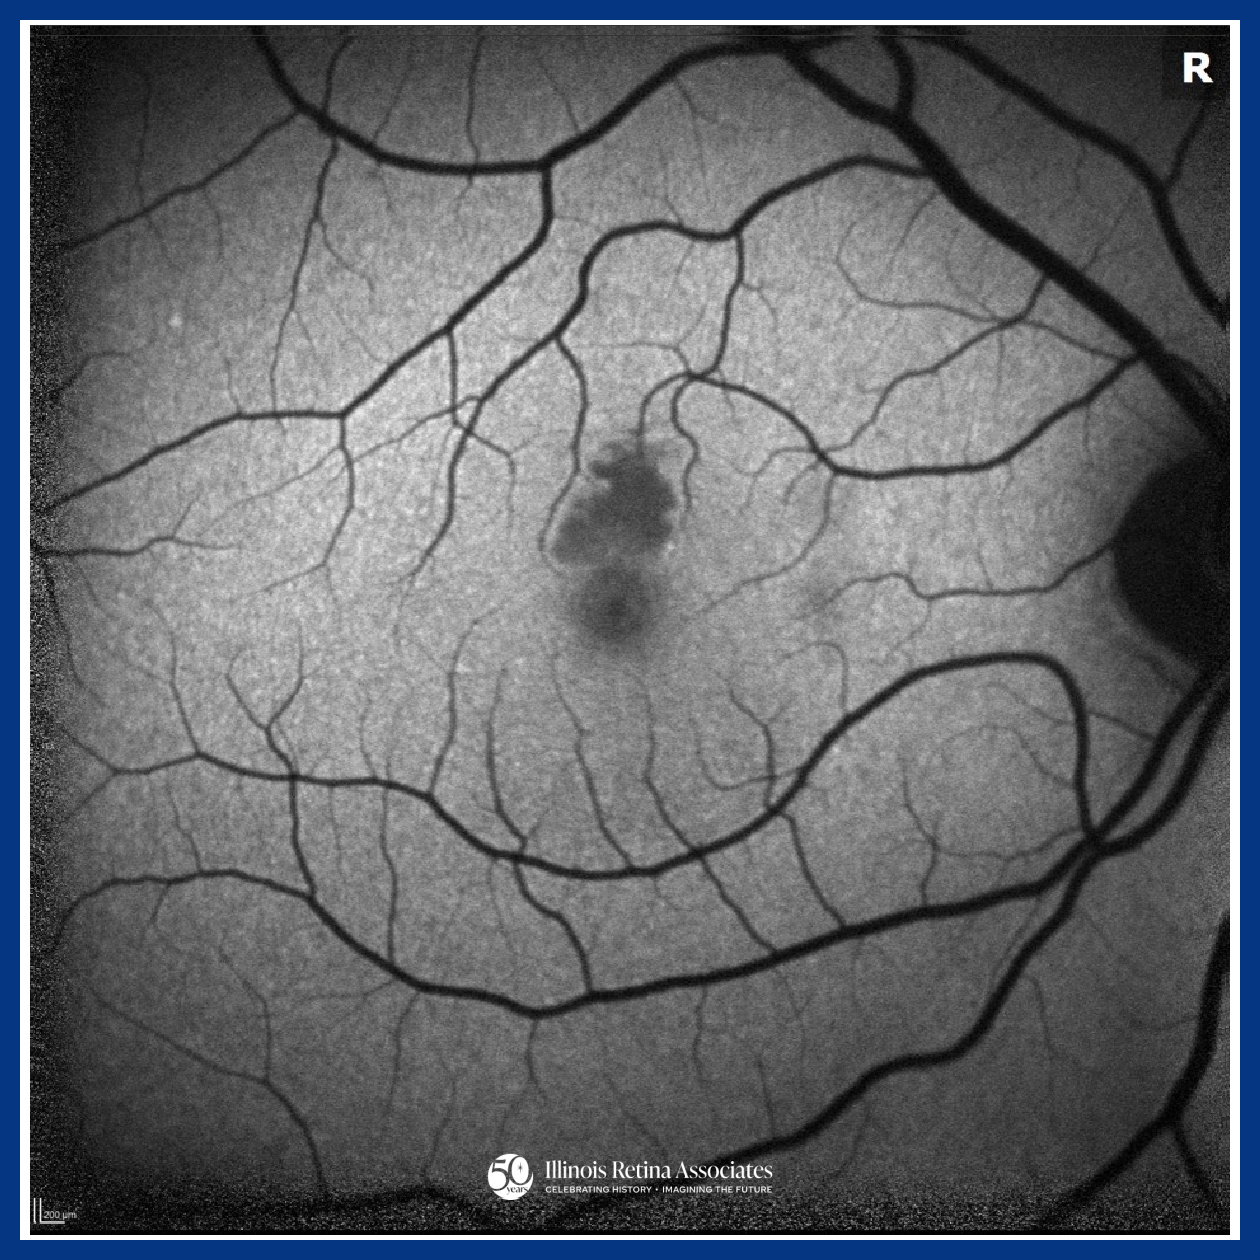

Visual acuity (VA) was 20/20 in both eyes (OU). Intraocular pressures and anterior segment exams were normal OU. Posterior segment exam OD demonstrated a cup to disc ratio (CDR) of 0.1 and a focal area of retinal whitening just superior to the fovea. Posterior segment in the left eye (OS) revealed a CDR of 0.1 and was otherwise unremarkable. Ocular Coherence Tomography (OCT) OD was significant for a band-like hyperreflectivity of the inner retinal layers (Fig 1) and FAF OD demonstrated mild hypo-autofluorescence overlying the area of retinal whitening (Fig 2). OCT OS was unremarkable (Fig 3). The patient was referred to the emergency department for a stroke evaluation which was negative. He returned approximately one week later where his VA remained stable at 20/20, and OCT showed slight improvement of the inner retinal hyperreflectivity (Fig 4). His central scotoma, however, remained unchanged.

PAMM is an ischemic macular disorder affecting the inner nuclear layer, often presenting with a sudden paracentral scotoma with minimal VA loss.1 PAMM can affect a wide-range of individuals from healthy patients to those with underlying systemic or retinal vascular disease, including arterial or venous occlusion, diabetes, or hypotension.2 Diagnosis is image-based: acute OCT imaging shows band-like hyperreflectivity of the inner nuclear layer, followed by focal thinning. FAF may be normal or show subtle hypo-autofluorescence. OCT-A can reveal capillary plexus flow deficits.3 While generally self-limited, paracentral scotomas may persist despite preserved visual acuity, reflecting permanent middle retinal ischemic injury.1